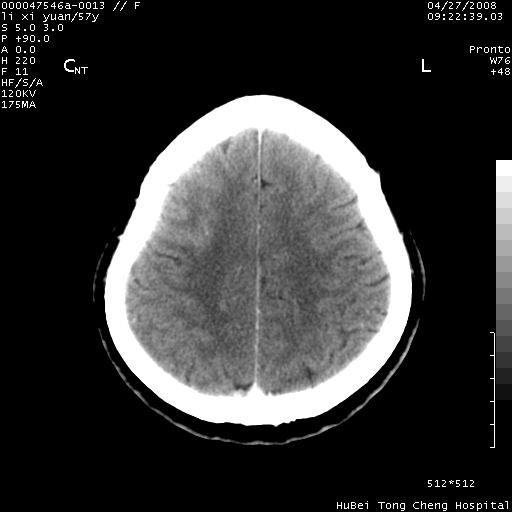

以下是引用余辉在2008-4-27 14:02:00的发言:[br]病灶位于中央沟前方?位于额叶?高密度灶,灶周水肿不明显,病灶似沿脑沟走行,强化明显,局部层面呈现环状强化,考虑1脑表面血管性疾病,如血管瘤,血管扩张,灶内血栓形成,其次考虑肿瘤如脑膜瘤、转移瘤,胶母等

以下是引用形影不离在2008-4-27 14:13:00的发言:[br]考虑胶质瘤可能性大,不排除慢性炎性肉芽肿。建议mri检查。